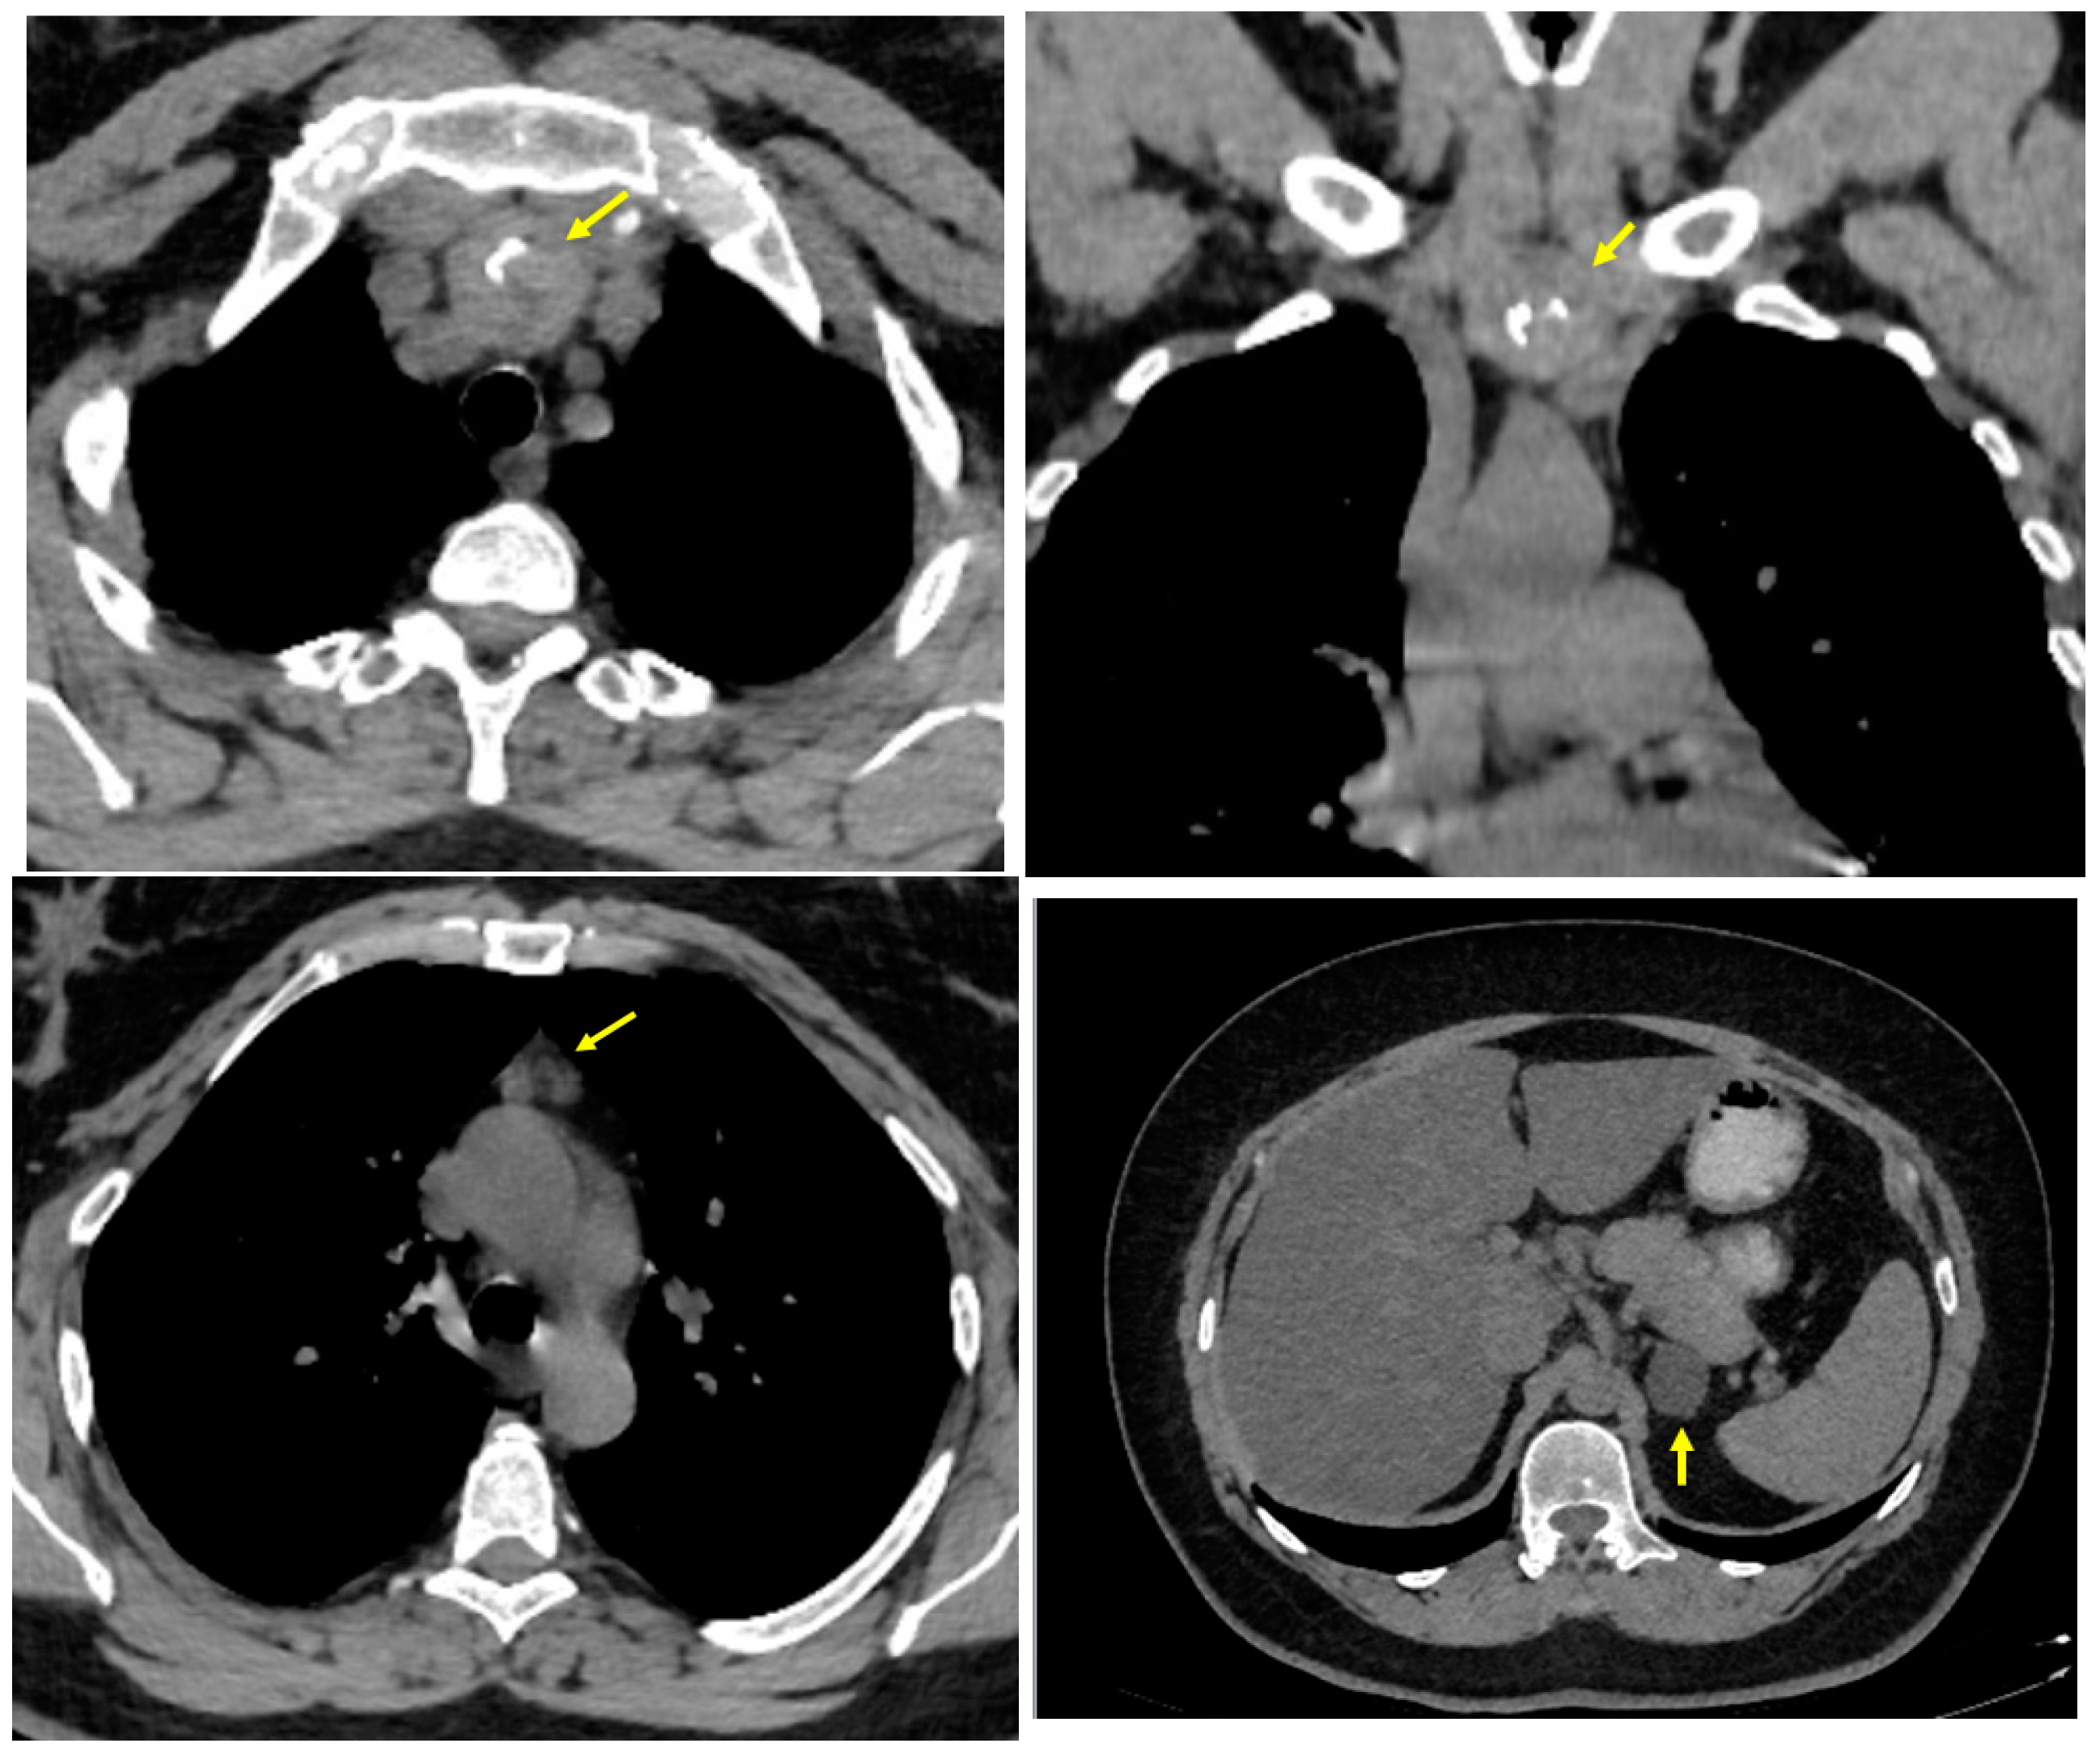

3.1.1. Baseline Admission: Identification of a Mediastinal Mass and an Adrenal Tumour Following Prior COVID-19 Infection

3.1.2. Endocrine and Imaging Investigations After One Year of Surveillance

3.2. Ectopic Mediastinal Thyroid Removal via Cervicotomy

- At the initial computed tomography, a small line of tissue was suspected to be the connective tissue between the orthotopic and ectopic thyroid, but it was not intra-operatory confirmed or after the post-surgery histological exam. This connective tissue facilitates the distinction between ectopic mediastinal tissue and a retrosternal extension of a cervical goitre [79];